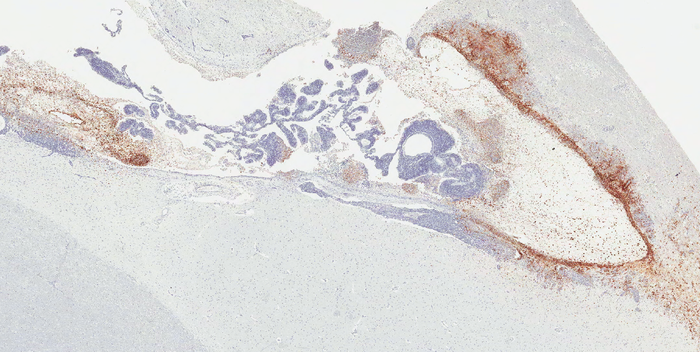

图片:埃博拉病毒(棕色)在一只恒河猴脑室系统和邻近神经系统中复发,这只恒河猴在感染埃博拉病毒后使用单克隆抗体治疗后存活下来。(细胞核反染成蓝色。)

Zeng解释说:“我们的研究首次揭示了埃博拉病毒在大脑中的隐藏位置,以及在非人灵长类动物模型中导致随后致命的复发性埃博拉病毒相关疾病的病理。”“我们发现,在接受单克隆抗体疗法治疗后,在致命的埃博拉病毒暴露下存活下来的猴子中,约有20%的猴子仍然存在持续的埃博拉病毒感染——特别是在脑室系统,脑脊液在该系统中产生和循环,甚至当埃博拉病毒从所有其他器官中被清除时。”

特别值得一提的是,有两只猴子在接受抗体疗法治疗后,从埃博拉病毒相关疾病中恢复过来,但出现了埃博拉病毒感染的严重临床症状,最终死亡。脑室系统出现严重炎症和大量埃博拉病毒感染;其他脏器未见明显病理及病毒感染。